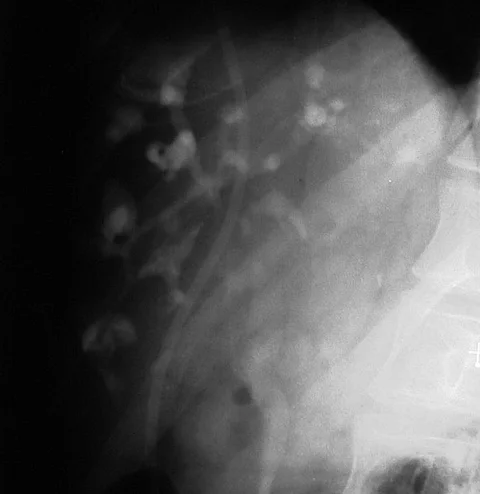

Quiz21-Jährige mit krampfartigen rechten Oberbauchschmerzen

Eine 21-jährige Patientin stellt sich mit wiederkehrenden, krampfartigen rechten Oberbauchschmerzen vor. In der Cholangiographie über eine Chiba-Nadel zeigen sich multiple zystische Strukturen, die mit den Gallengängen in Verbindung stehen. Die Gallengänge selbst erscheinen segmental dilatiert.